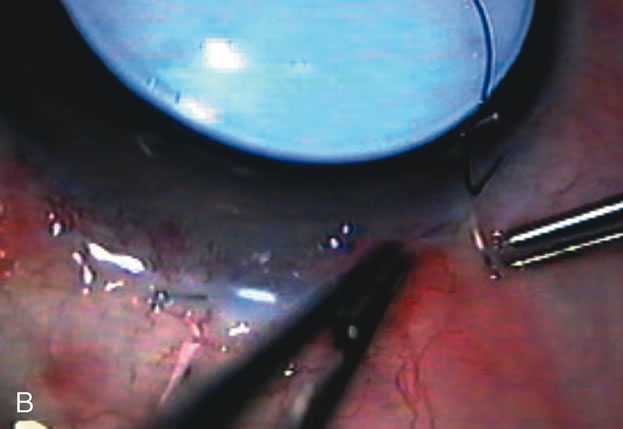

Fig. 1. The anatomic advantage of small incision cataract surgery for the glaucoma patient. A. Long-term bleb function with a large cataract incision is difficult to achieve with either ECCE-trabeculectomy or trabeculectomy followed later by ECCE. This bleb failed to form sufficiently when combined with large incision ECCE. The inflammation, bleeding, and long-term wound healing with stimulation of fibroblasts associated with this technique are more likely to cause bleb failure. In addition, the increased iris manipulation necessary to deliver the nucleus and subsequent iris repair adds to the long-term breakdown of the blood aqueous barrier. B and C. Two-site phacotrabeculectomy has the advantage of small incision cataract surgery combined with separate site trabeculectomy. The incision size is one third the size of the standard ECCE. The inflammation is less severe, and cataract wound healing is confined to the temporal area. Visual rehabilitation with phacoemulsification and foldable IOL is much faster. Phacoemulsification allows successful lens extraction even in the unfriendly environment of a smaller pupil compared with ECCE. The trabeculectomy is performed in an entirely different site, well away from the wound healing associated with temporal phacoemulsification. The likelihood of this filter functioning long-term is greater than with ECCE-trabeculectomy. D. The surgeon also has the option of single-site phacotrabeculectomy with foldable IOL. Both the lens extraction and trabeculectomy are performed through one small 3.5-mm limbal incision.

Fig. 3. Partial bleb failure following clear corneal phacoemulsification with foldable IOL. A. Preoperative bleb appearance prior to temporal lens extraction. Preoperative IOP was 12 mm Hg on no antiglaucoma medications. Time from 5-FU trabeculectomy surgery to lens extraction was one year. B. Bleb appearance 2 months after clear corneal cataract surgery with topical anesthesia. Following lens extraction, increased vascularity was noted along with decreased size of the filtering bleb. IOP increased to 20 mm Hg as early as 2 weeks after surgery, necessitating topical antiglaucoma therapy. C. High magnification view of bleb before lens extraction demonstrates diffuse pale bleb. D. High magnification view of bleb 2 months after surgery. There are vessels surrounding the nasal side of the bleb and the overall bleb size is smaller.